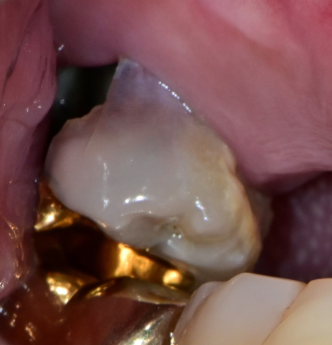

3. 충치가 치근 아래까지 진행된 경우

치아 머리 부분이 거의 남지 않고

충치가 뿌리까지 퍼진 경우엔

보철물로 복원하더라도 기능이 약해 오래 사용하지 못합니다.

이럴 땐 무리한 치료보다

예후가 좋은 임플란트를 고려해보는 것이 현명합니다.